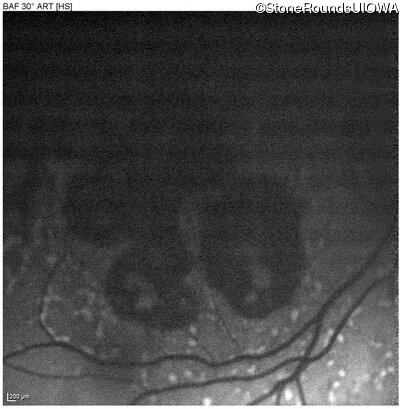

Blue Autofluorescence - Left - 20/25 -2

Exemplar